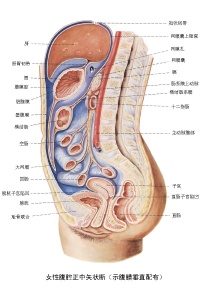

腹膜(peritoneum)为全身面积最大、配布最复杂的浆膜,由皮及少量结缔组织构成,薄而光滑,呈半透明状。

衬于腹、盆腔壁内表面的腹膜称为壁腹膜(parietal peritoneum)或腹壁薄层;

覆盖腹、盆腔器表面的部分称为脏腹膜(visceral peritoneum)

脏腹膜与壁腹膜互相延续、移行,共同围成不规则的潜在性腔隙,称为腹膜腔(peritoneal cavity)。

腹膜腔是脏、壁两层腹膜之间相互移行围成的潜在性间隙。腹膜腔内有少量浆液,在脏器活动时可减少摩擦。

男性腹膜腔为一封闭的腔隙;女性腹膜腔则藉输卵管腹腔口经输卵管、子宫、阴道与外界相通。

壁腹膜较厚,与腹、盆壁之间还存有一层疏松结缔组织,称为腹膜外组织。

在腹后壁及腹前壁下部的腹膜外组织中含有较多脂肪。脏腹膜紧贴覆于脏器表面,从组织结构和功能方面都可视为器官的一部分,如胃、肠壁最外层的浆膜即为脏腹膜。

腹、盆腔的脏器依据被覆腹膜的多少可分为三类即:

此类器官几乎全部包被腹膜,活动度较大。主要的器官有:胃、十二指肠

上部、空肠、回肠、阑尾、横结肠、乙状结肠、脾、卵巢、输卵管等。

此类器官三面包被腹膜,活动度较小。主要的器官有:升结肠、降结肠、肝、膀胱、子宫等。

此类器官只有一面包被腹膜,几乎不能活动。主要的器官有:胰、肾、输尿管、肾上腺等。